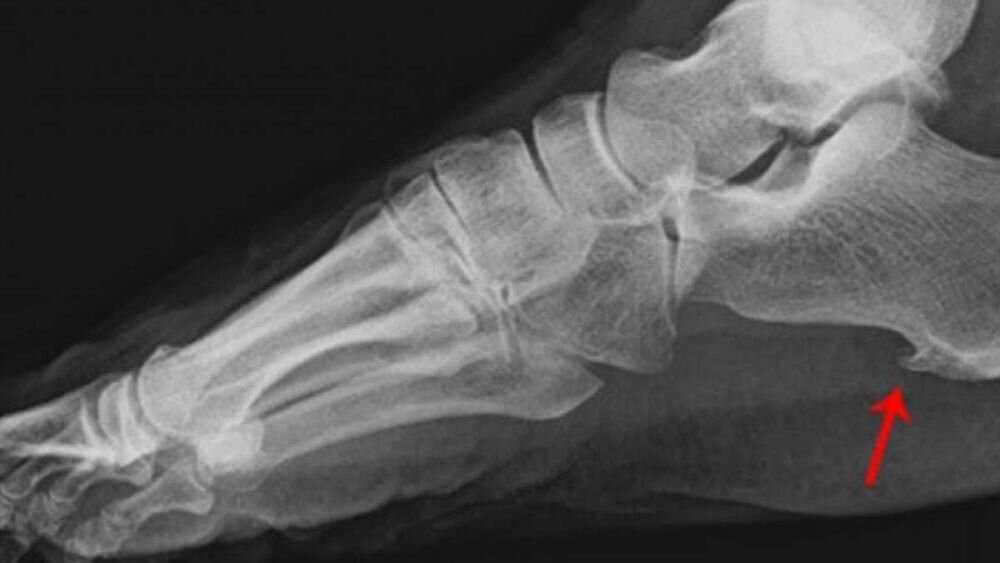

Основной жалобой является резкая боль в области пятки при ходьбе, беге, при выполнении упражнений и действий, которые предполагают нагрузку на стопу. Среди других признаков наличия болезни — появление болезненных ощущений утром после пробуждения. На начальной стадии боль обычно быстро проходит после выполнения каких-либо упражнений. На поздней — болезненные ощущения становятся более продолжительными, дискомфорт может возникать даже в состоянии покоя. Покалывание в области пятки, ощущение сильного жара, появление покраснений также может указывать на наличие пяточной шпоры. Выявить проблему самостоятельно можно, если провести диагностику. Повышенная чувствительность при надавливании стопы при пяточной шпоре в месте прикрепления сухожилия на пятке является одним из признаков заболевания. Для постановки точного диагноза необходимо обратиться к специалисту. Пяточная шпора диагностируется на рентгеновском снимке.

Пяточная шпора — плотный костный нарост на пятке. В большинстве случаев проблема появляется в области, расположенной от точки нижнего переднего края пяточной кости и проходит вдоль подошвы стопы к пальцам. Это заболевание называется подошвенная пяточная шпора. Нарост, который возникает в месте прикрепления tendon Achillis— Ахиллова сухожилия, более редкая форма — это дорсальный тип пяточной шпоры. Причины появления заболевания связывают с чрезмерными нагрузками. Хронические микротравмы в области прикрепления сухожильных пластинок нижней пяточной кости, вызванные длительным растяжением мышц и связок, приводят к накоплению солей кальция в тканях организма — кальцификации и в дальнейшем к окостенению пораженного участка.